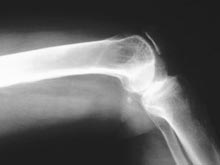

Многие люди с поражениями костей и суставов могут получить новую жизнь с пересадкой костной ткани. И ключевую роль здесь играют костные банки, где в специальных морозильных камерах хранится собранный во время операций тщательно измельченный, обработанный и стерилизованный костный материал. Чаще всего в банк поступает материал головки бедренной кости, которая удаляется во время операции по эндопротезированию.

"Пациент всегда решает сам, будет ли его костная ткань, удаленная во время операции, уничтожена или пожертвована для использования в дальнейшем в лечении других пациентов. При проведении операции по эндопротезированию нужно всегда быть готовым к использованию материала костного банка, а при проведении ревизионной операции это, более того, является необходимостью. Благодаря использованию материала банка при операциях по исправлению сколиоза можно избежать трансплантации собственной кости пациента", - рассказывает Саули Варьенен, хирург-ортопед финской клиники Orton.

Материалы из банка обычно используются при проведении сложных хирургических операций по замене сустава. Материал позволяет реконструировать костные дефекты вокруг протеза. Также материалы нужны в операции спондилодеза по исправлению сколиоза у молодых людей, в том числе идиопатического. Донорская костная ткань довольно быстро прорастает кровеносными сосудами и превращается в собственную кость пациента. Донорская ткань абсолютно безопасна - она подвергаются бактериологической проверке, тщательно исследуется состояние здоровья донора.

В свою очередь, пересадка собственной кости пациента вызывает ряд проблем. Это и увеличение продолжительности операции, и большая потеря крови, и выраженный болевой синдром. Поэтому донорский материал выглядит более привлекательно.